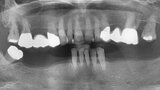

Počítačem asistované, šablonou se řídící okamžité zavedení a zatížení implantátu v dolní čelisti